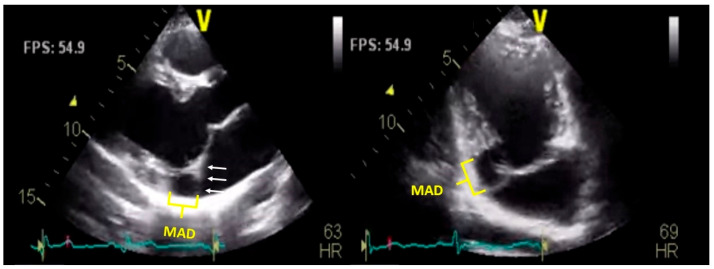

二尖瓣环分离(MAD)是一种越来越被认可的二尖瓣结构异常,通常与二尖瓣脱垂和室性心律失常和心源性猝死的风险增加有关。它是由二尖瓣环和左心室心肌之间的分离来定义的,在收缩期最明显。在这篇综述中,我们从最近的大规模影像学研究、专家共识文件和新提出的分类(如真与伪MAD)中,对MAD进行了更新和全面的概述。我们讨论了它的患病率、解剖特征和多种成像方式的诊断挑战,包括经胸和经食管超声心动图、心血管磁共振和计算机断层扫描。我们还探讨了其在心律失常发生中的病理生理作用,其预后意义和当前的管理策略。特别关注基于影像学和心律发现的风险分层,我们提出了一个实用的临床框架来指导决策。本综述旨在支持临床医生认识到MAD是一种潜在的致心律失常疾病,需要系统的评估和随访。

Mitral annular disjunction (MAD) is an increasingly recognized structural abnormality of the mitral valve apparatus, often associated with mitral valve prolapse and a heightened risk of ventricular arrhythmias and sudden cardiac death. It is defined by a separation between the mitral annulus and the left ventricular myocardium, best visualized during systole. In this review, we present an updated and comprehensive overview of MAD, drawing from recent large-scale imaging studies, expert consensus documents, and newly proposed classifications such as true versus pseudo-MAD. We discuss its prevalence, anatomical features, and diagnostic challenges across multiple imaging modalities, including transthoracic and transesophageal echocardiography, cardiovascular magnetic resonance, and computed tomography. We also explore its pathophysiological role in arrhythmogenesis, its prognostic implications, and current management strategies. Special attention is given to risk stratification based on imaging and cardiac rhythm findings, and we propose a practical clinical framework to guide decision-making. This review aims to support clinicians in recognizing MAD as a potentially arrhythmogenic condition that requires systematic evaluation and follow-up.